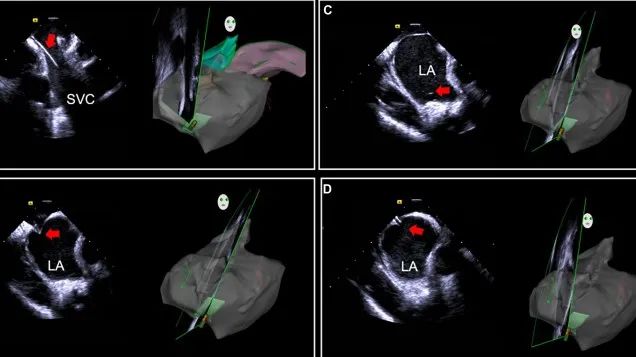

一種與心導(dǎo)管檢查相結(jié)合的超聲心動(dòng)圖診斷新興技術(shù),通過將超聲探頭置于心腔內(nèi)部,發(fā)射并接收超聲信號(hào),來(lái)精確獲取心臟解剖結(jié)構(gòu)、心臟血流動(dòng)力學(xué)等信息的實(shí)時(shí)成像。與其他影像技術(shù)相比,ICE技術(shù)具有操作簡(jiǎn)單、無(wú)輻射、安全性高、手術(shù)效率高、實(shí)用等優(yōu)勢(shì),ICE在很大程度上有望取代經(jīng)食道超聲心動(dòng)圖(TEE),成為電生理和結(jié)構(gòu)性心臟病領(lǐng)域的理想成像方式。

心腔內(nèi)超聲(ICE)技術(shù)壁壘極高,國(guó)內(nèi)主要廠商核心部件仍舊為進(jìn)口,集成了超聲和圖像處理最前端技術(shù),包括超聲探頭、線纜、軟件成像算法等,是當(dāng)前內(nèi)窺超聲方向最具挑戰(zhàn)的領(lǐng)域。ICE的應(yīng)用經(jīng)歷了2D平面成像、3D三維立體成像、以及4D的實(shí)時(shí)三維立體成像階段。